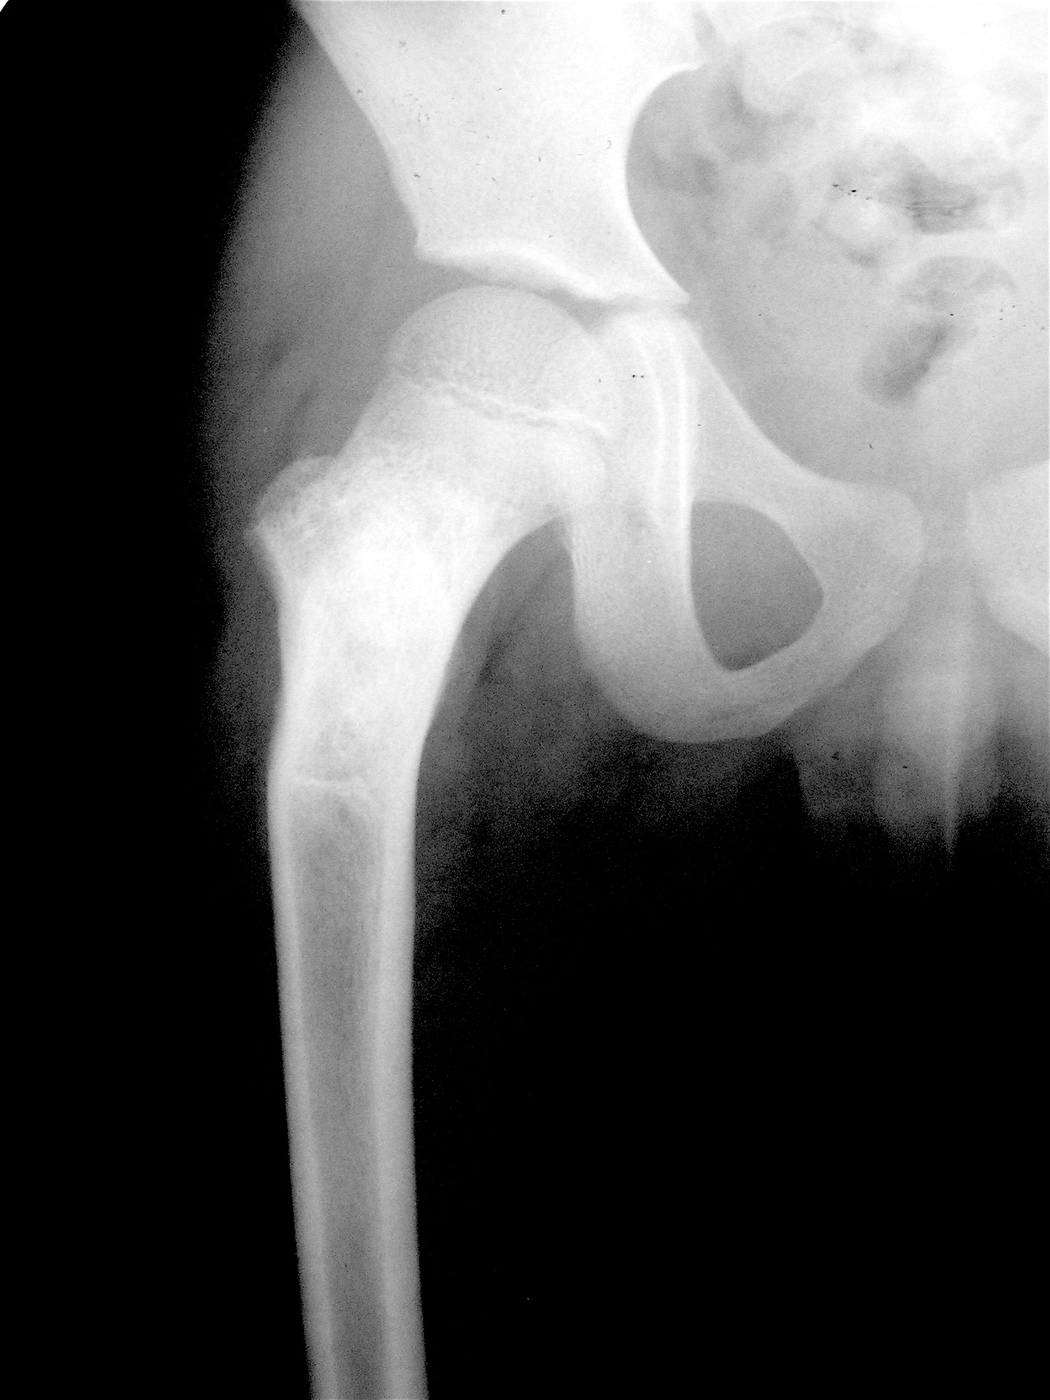

Закрытый патологический перелом шейки левой бедренной кости и проксимального метафиза бедренной кости на фоне аневризмальной костной кисты.

Аллопластика материалом «Лиопласт».